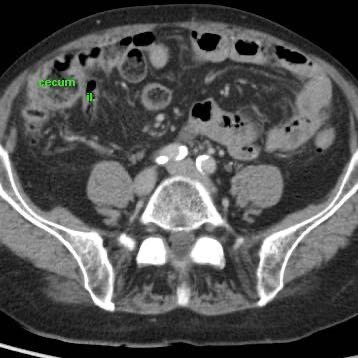

Dấu hiệu gián tiếp của viêm ruột thừa

Ở những bệnh nhân không thể quan sát được ruột thừa trên siêu âm và cũng không tìm thấy bệnh lý thay thế nào, các dấu hiệu gián tiếp của viêm ruột thừa có thể hữu ích.

CT xác nhận tình trạng giải phẫu.